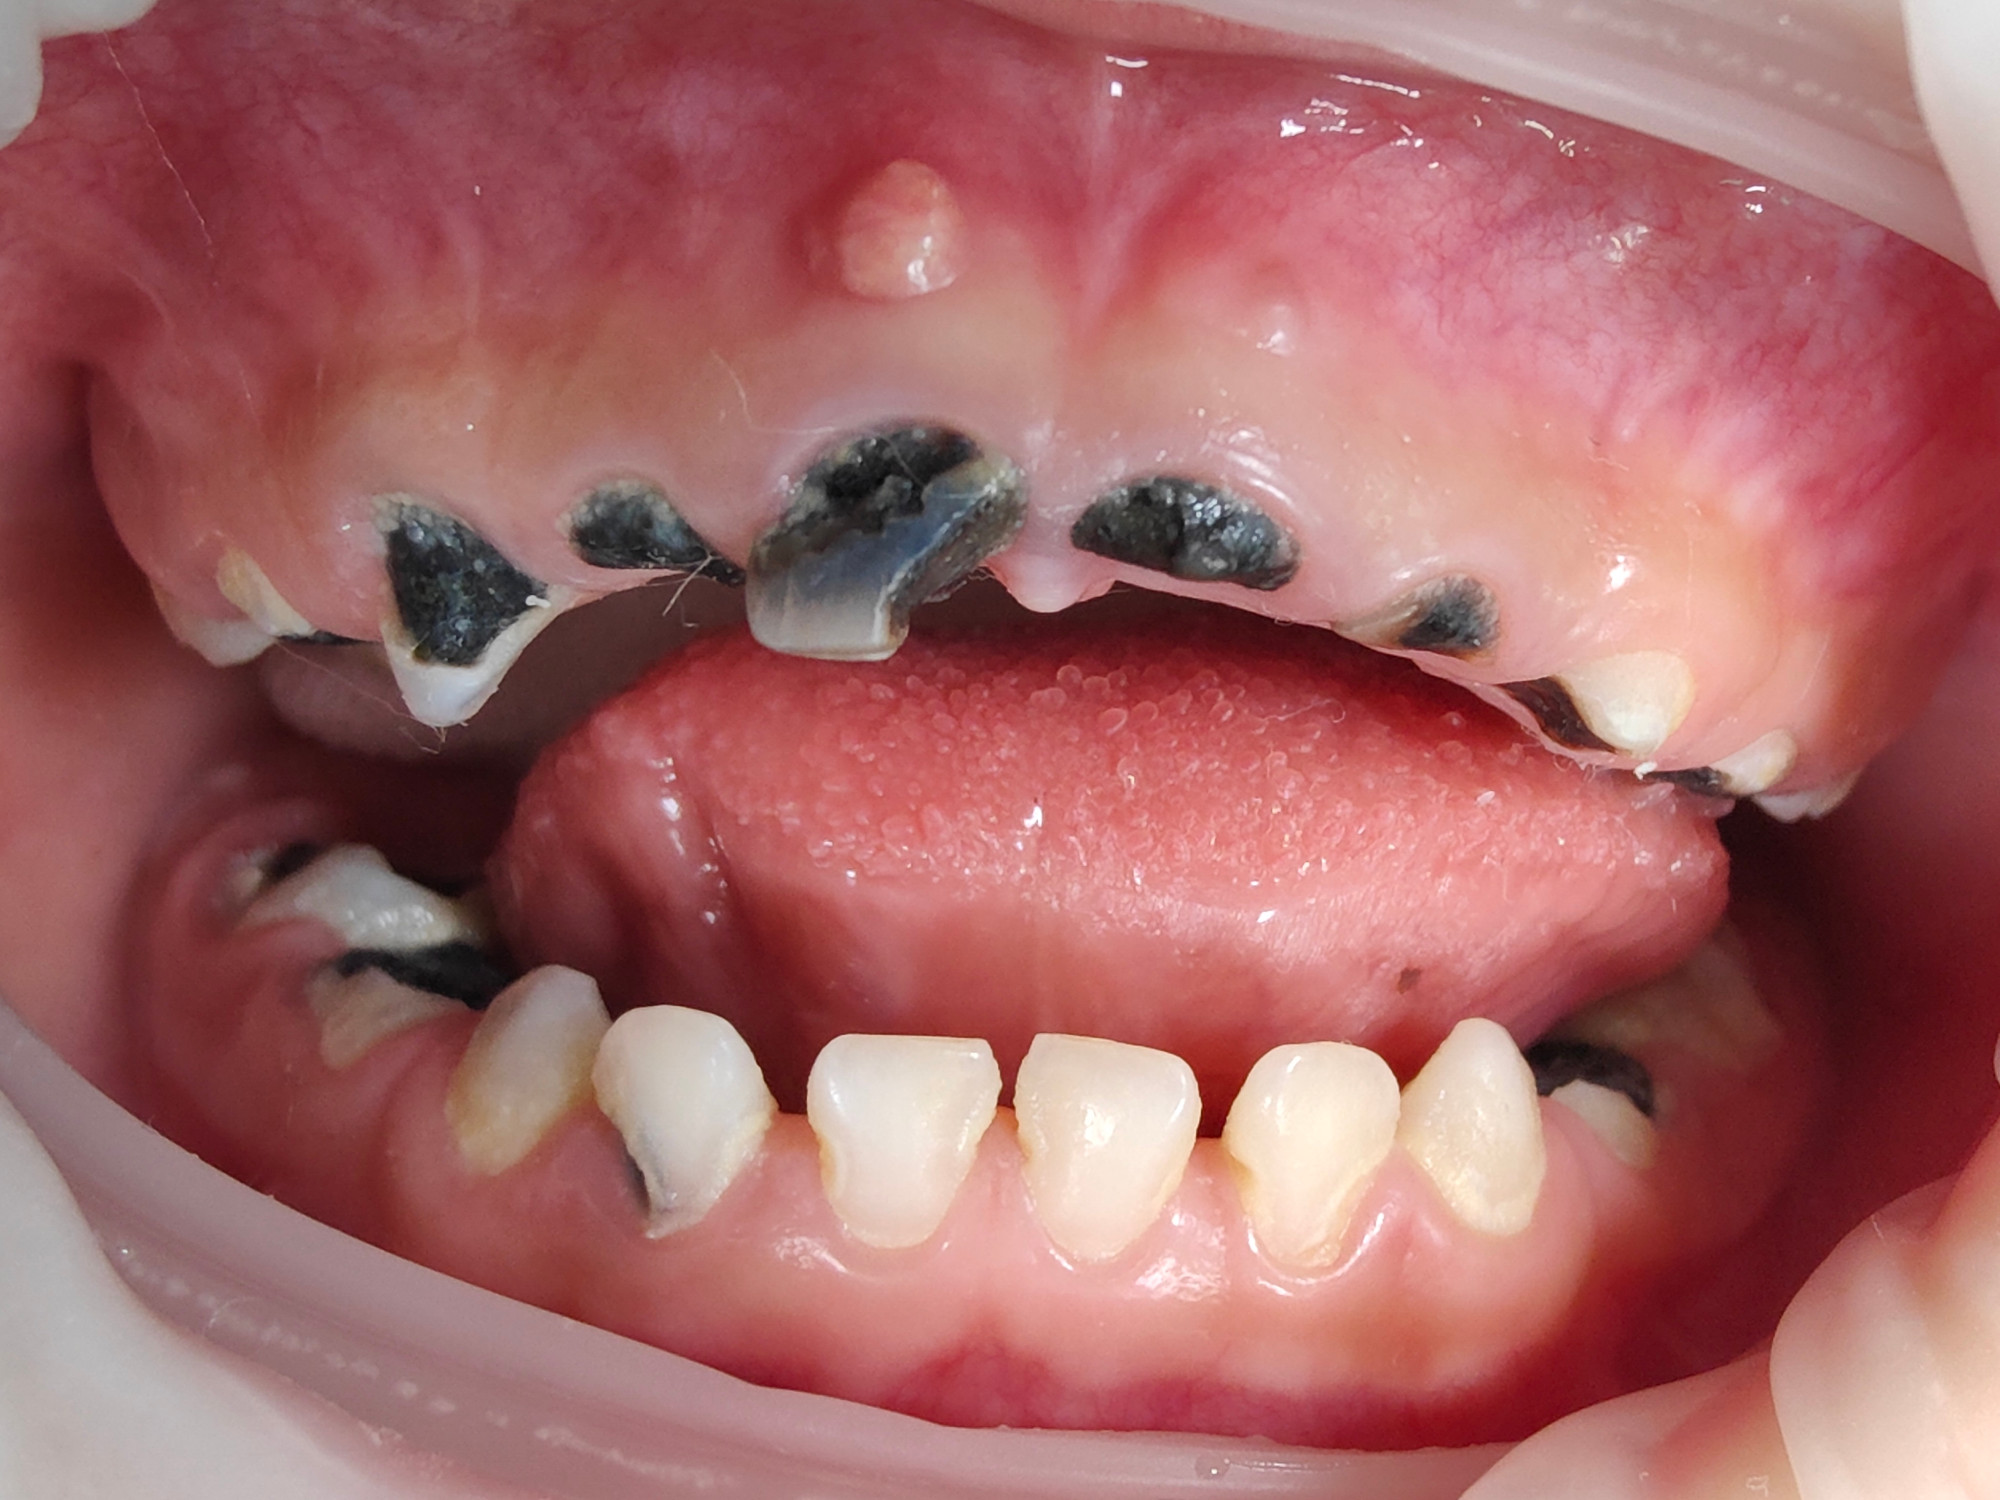

乳牙龋齿,也被称为“虫牙”,是儿童时期最常见的口腔疾病之一。许多家长认为乳牙迟早会被恒牙替换,不必太在意,但事实上,乳牙龋齿不仅会影响孩子的进食、发音和外观,还可能对恒牙的发育造成长期影响,因此必须重视。

乳牙龋坏不仅仅是“黑点”或“蛀洞”,其危害远不止疼痛:

2. 影响恒牙发育:乳牙下方正是恒牙牙胚所在位置,龋齿感染可波及牙胚,引起恒牙发育异常或色素沉着。